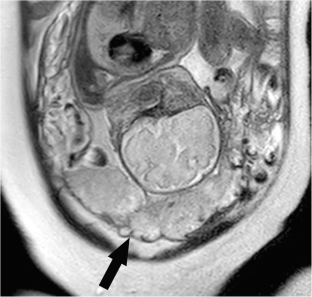

Fig. 1

Fig. 2

Fig. 3

Fig. 4

Fig. 5

Fig. 6

Fig. 7

Fig. 8

Fig. 9

Fig. 10